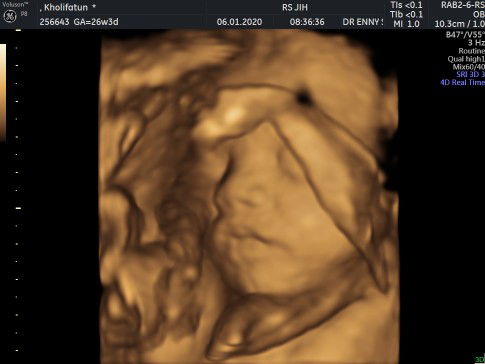

Pengalaman USG 4D usia 26W3D

Untuk pertama kalinya USG 4D, karena dokter dan perawat selalu menyarankan USG 4D lebih baik dilakukan saat usia kandungan sudah lebih dari 6bulan. Padahal dari usia 4 bulan sejak debay mulai suka nendang rasanya penasaran banget dan saat itu juga pengeeennn bangeeettt USG 4D, lihat di medsos juga banyak mommy yg USG 4D padahal usia masih dibawah 6bulan (makin pengen). Tapi dokternya tetep bilang nunggu 6 bulan aja ya, baik dok? Aalhamdulillah... kemarin sudah dibolehin 4D (seneng banget) ? jadiii hari sebelum USG sempet tanya syaratnya apa aja, ternyata sebelum melakukan USG harus makan yg manis dulu, kemudian saat periksa disuruh bawa 2 cup ice cream. Aku sih pokoknya siap aja, padahal blm tau buat apa coba bawa ice cream (maklumnya baru pertama kalinya jadi serba gatau gitu)? Sampai dilokasi baru tanya langsung sama perawatnya, dan dijelasin fungsinya ice cream itu supaya keliatan si debaynya dan aktif pergerakannya ?? terharu & seneng banget untuk pertama kalinya bisa lihat wajah debay diperut? Kayaknya ini ekspresi saat lagi menikmati ice cream ya, bibirnya sampe manyun gitu ?